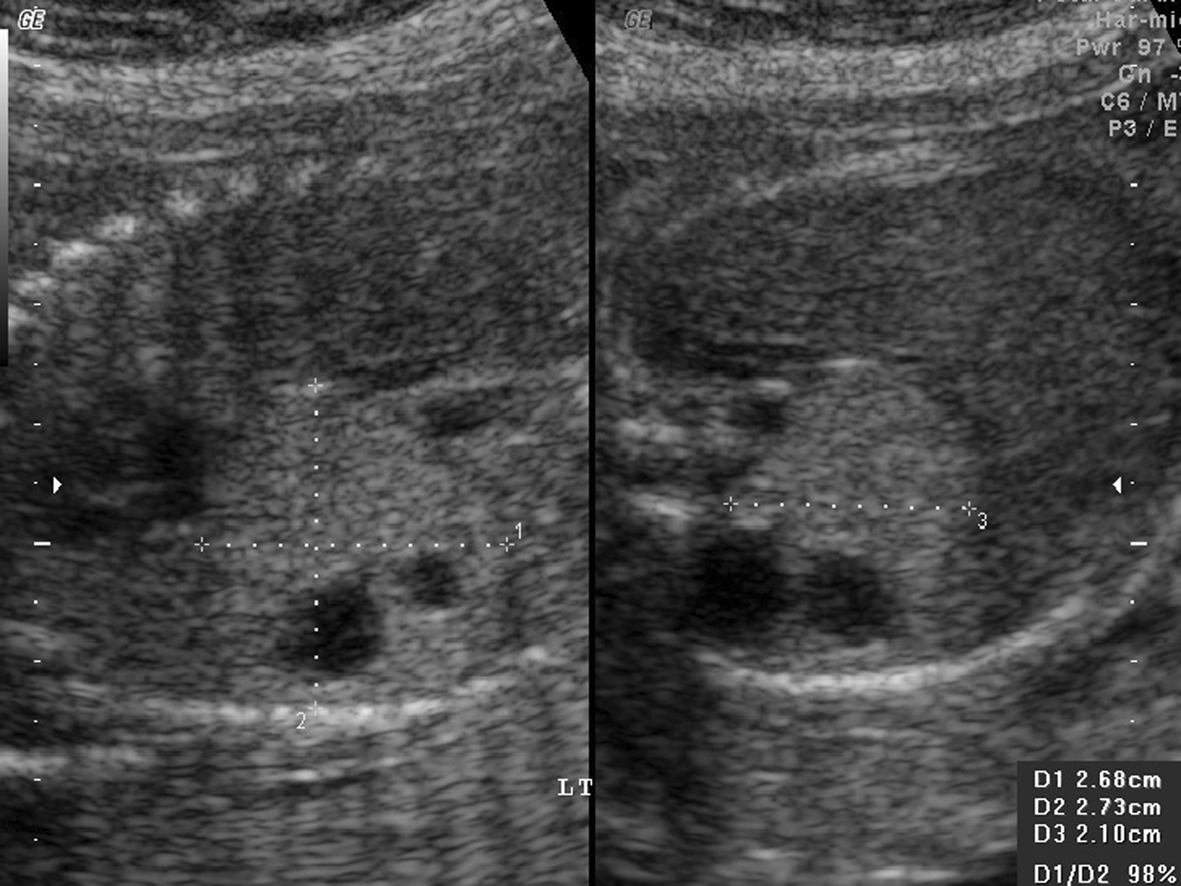

1.胎儿肺部异常 ①I型(大囊肿型):胸腔内见囊性或囊实混合性肿块,囊肿直径≥2 cm(图1);②Ⅱ型(小囊肿型):胸腔内见囊实混合性肿块,囊肿直径在5mm~2 cm间(图2);③III型(实质型或微囊肿型):胸腔内强回声实性肿物,与正常肺组织边界清晰,使用高频探头可观察到强回声实性肿块内部弥漫分布筛孔状无回声区,最大囊肿直径<5 mm(图3、4)。

图2 左侧CCAM II型,孕23周6天,胸腔发现混合性占位性病灶